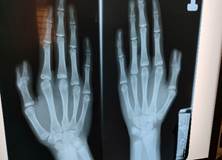

Khám lâm sàng: ngón tay cái trái có hai trụ, trong đó trụ ngoài (ngón phụ) nhỏ hơn, hạn chế vận động, trụ trong phát triển gần bình thường. Biến dạng ảnh hưởng đến chức năng và gây mặc cảm cho bệnh nhân khi giao tiếp xã hội. Chẩn đoán hình ảnh (X-quang): dị tật ngón cái đôi, type II theo phân loại Wassel (tách đôi từ nền đốt gần).

- Hình 2: X-quang bàn tay cho thấy tách đôi ngón cái từ nền đốt gần (Wassel type II).